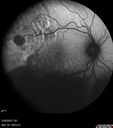

58 year old female The patient noticed decreased vision in the right eye about 2.5 months ago. (you may want to omit this initially -> ) 3 months ago she found a lump in her breast and had stage IV cancer which had spread. It is in her bone, lung. She is starting radiation tomorrow on a couple of vertebrate. Medical Hx: (Onset: 3/28/2023). Breast Cancer Stage 4. Hypertension, Systemic. Surgical Hx: Tonsillectomy. C-Section. Systemic Meds: Propranolol Hydrochloride, 80 mg oral tablet qday. PROCHLORPERAZINE 10MG qday. ANASTROZOLE 1 mg ORAL TABLET, FILM COATED [Anastrozole] qday. Dexamethasone 400 MCG/0.1ML PFS qday. VA OD: Dcc20/200 VA OS: Dcc20/63 IOP: TP: OD:12 OS:15 Put breast cancer history here: Had 10 sessions of radiation to the right eye starting 4/2023 and ending 04/26/23. Also - 4/2023 - kisqali and letrosole (forever drugs) 12/12/23 - Retinal detachment almost completely resolved – Exudative RD took 8 months to resolve. – VA improved from 20/200 to 20/40 (last visit)

Choroidal Metastatic Breast Cancer with Exudative Detachment109 views58 year old female presented with 20/200 vision. Had 10 sessions of radiation and tumor shrank. The exudative detachment took almost a year to resolve. The vision improved to 20/40.00000